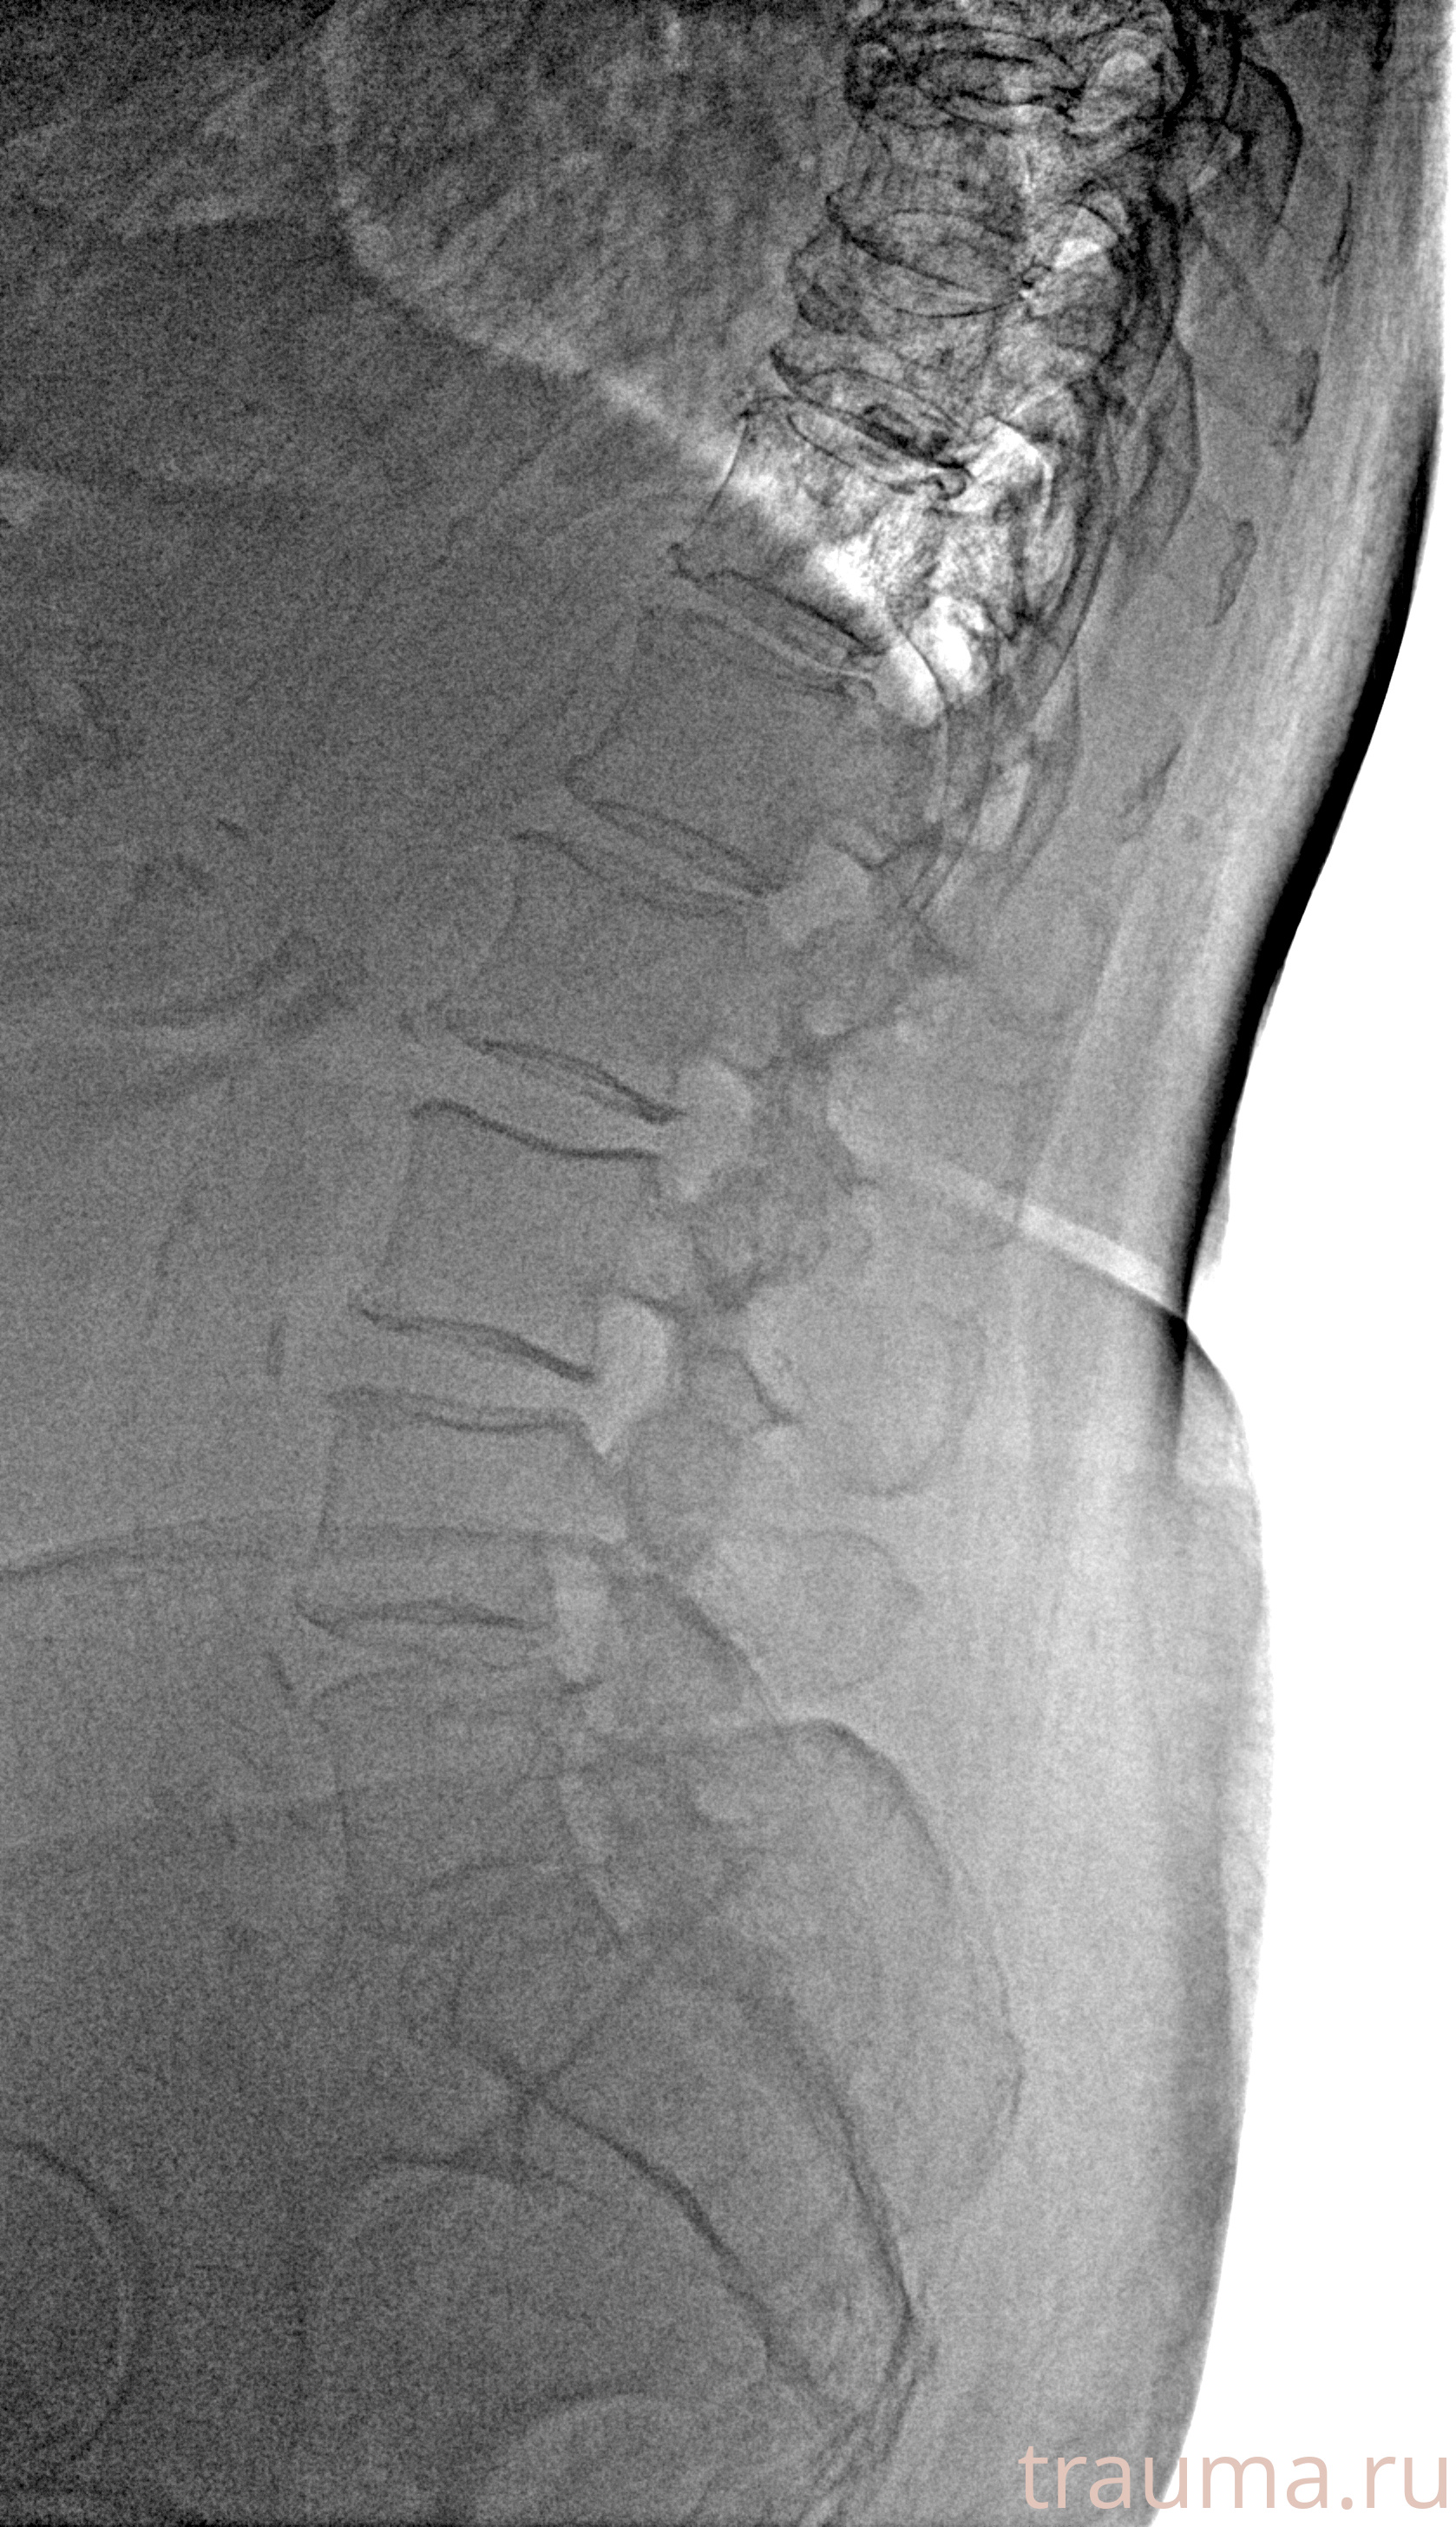

Рентгенограммы

Рентген на дому: по вашему адресу приезжает врач-рентгенолог, травматолог-ортопед с мобильным рентгеновским аппаратом, проводит диагностику травмы или заболевания, делает необходимые рентгенограммы, дает рекомендации по дальнейшему лечению. Получить качественные снимки в домашних условиях возможно благодаря уникальной методике, разработанной МосРентген Центром для института  Склифосовского